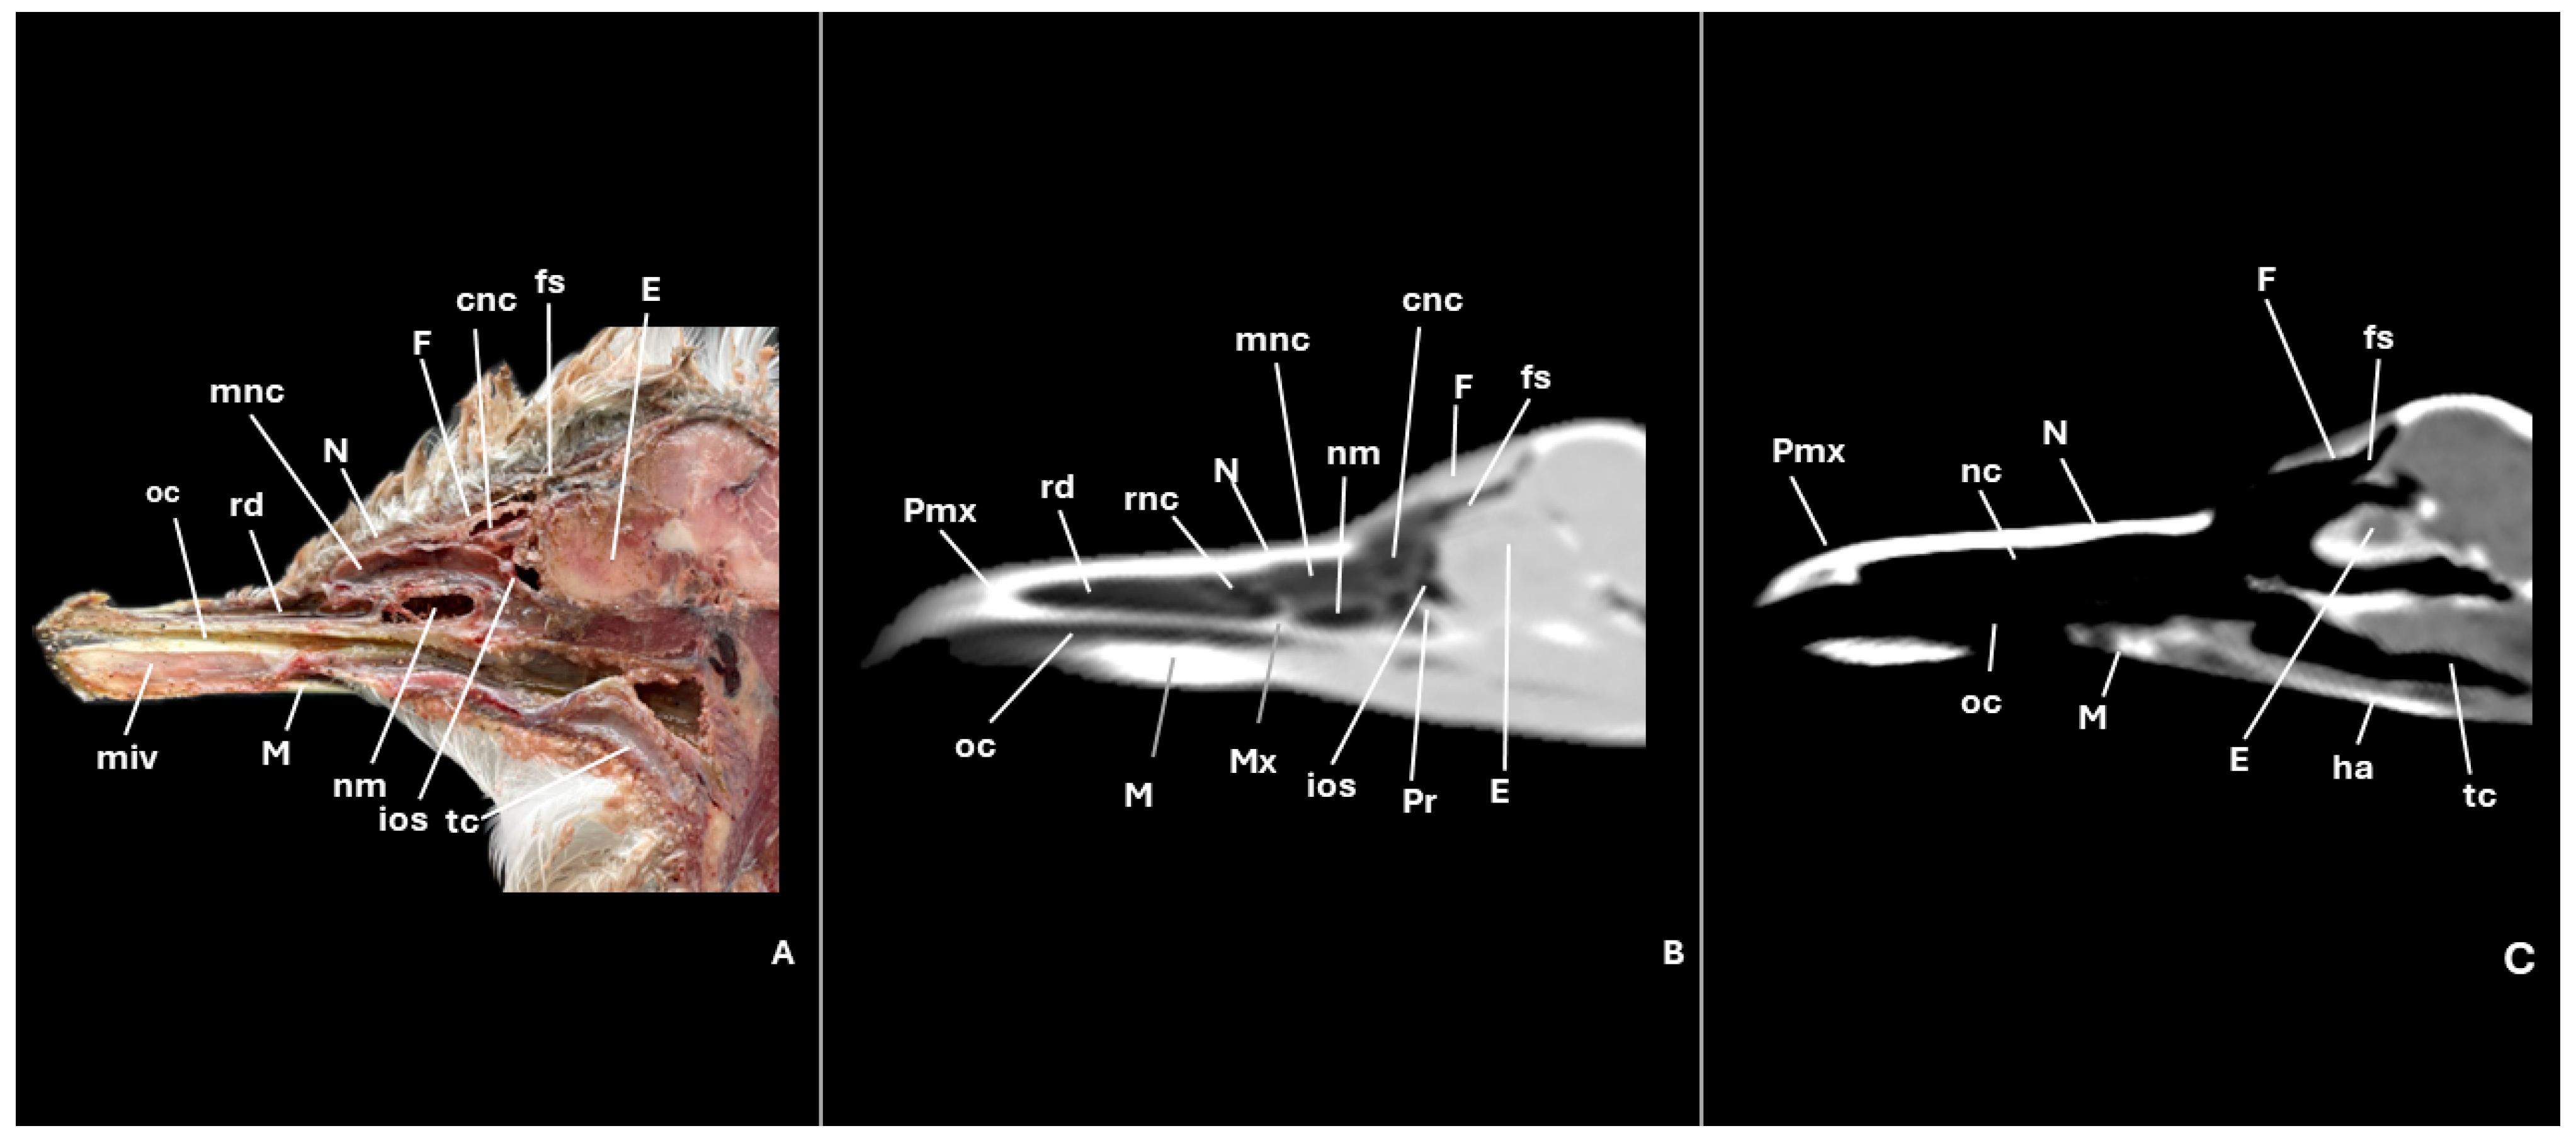

3.1. Anatomical Cross-Sections

3.2. Computed Tomography (CT)